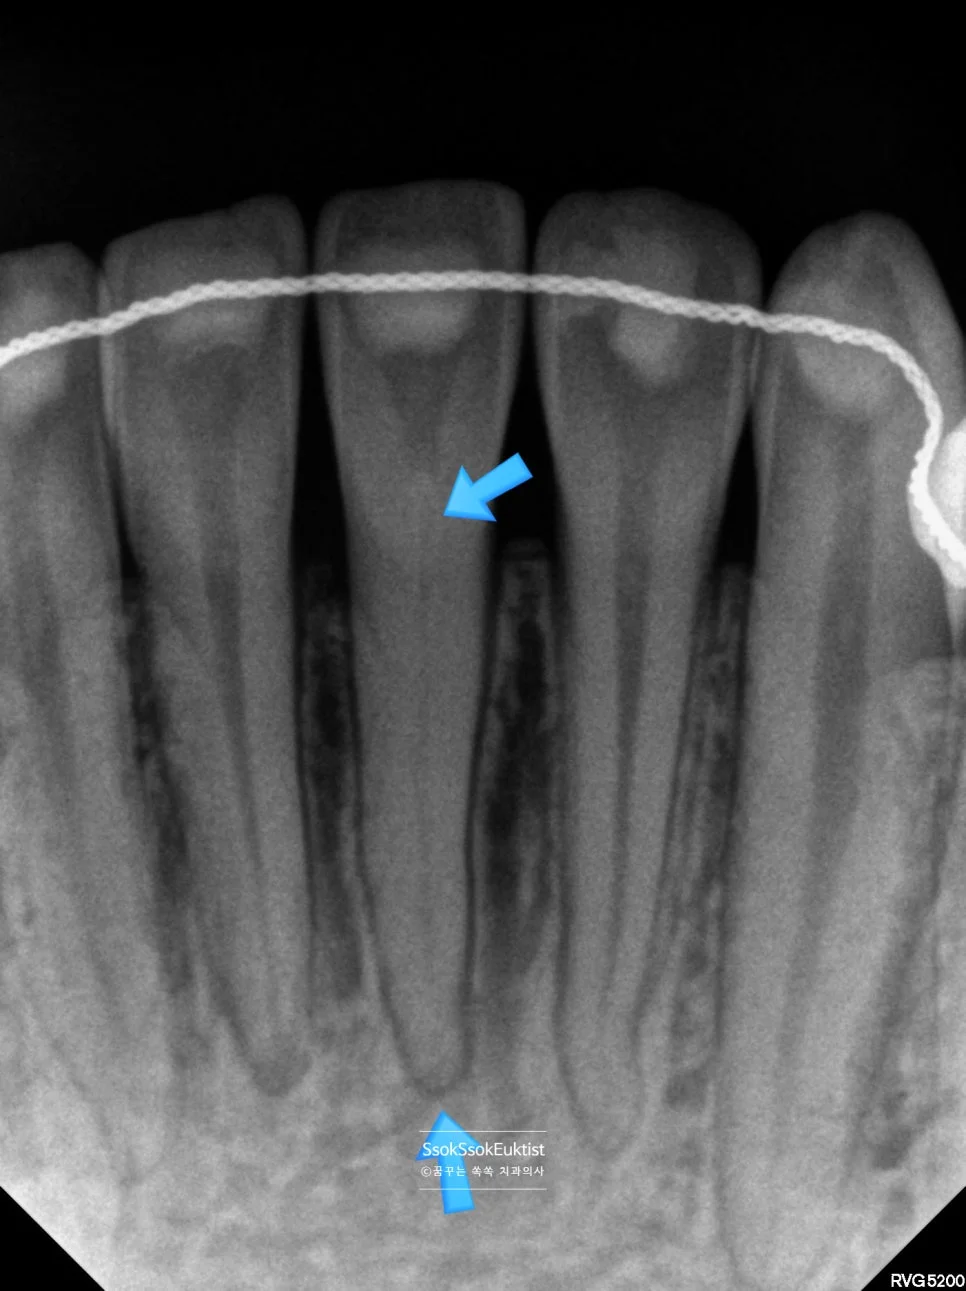

변색된 실활치 (화살표) — 다른 치아 대비 보라색/갈색 느낌이 짙은 상태

그림에서 화살표로 표시한 치아 색이 왜 이럴까요? 다른 치아 대비 보라색? 갈색? 느낌이 짙은데요. 이 치아가 바로 치아의 신경이 괴사된 실활치입니다.

진단 X-ray — 다른 치아에 비해 신경관(검은 음영)이 매우 좁아져 있는 모습

해당 치아의 X-ray를 촬영해 보면 다른 치아들에 비해 신경관(검은 음영)이 매우 좁아져 있는 모습인데요.

신경 조직이 오랫동안 자극을 받으면서 자극에 대한 방어기제로 신경관이 좁아진 것입니다. 그간 얼마나 아팠을까요ㅜ